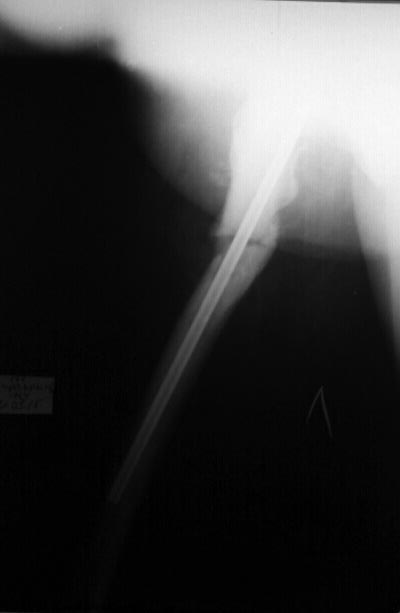

[Ortho] мраморная болезнь

Уважаемые коллеги, больную готовим к операции совместно с эндокринологом

и терапевтом (диабет, анемия). Кстати сделали снимок в боковой проекции